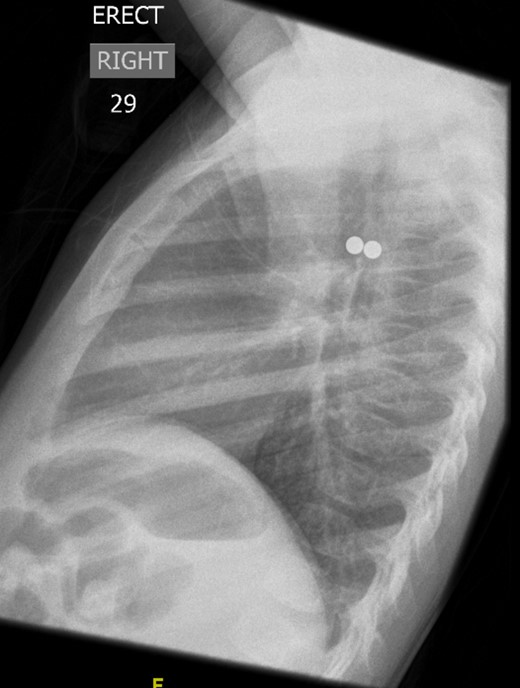

A 3-year-old girl was referred to the asthma clinic with a 3-month history of morning cough and wheeze. She was seen multiple times by her general practitioner (GP) who initially diagnosed her with upper respiratory tract infection. Her symptoms persisted despite salbutamol inhaler treatment so the GP organised a chest x-ray (CXR) (Fig. 1). It was reported that the left lung was translucent with reduced peripheral lung markings: finding consistent with asthma with bronchial plugging or a post infective bronchiolitis. It also showed a round radio-opaque FB over the left main bronchus. However, this was labelled as ‘Clothing Artefact’ on the actual radiograph and therefore did not alarm the GP or the reporting radiologist. A repeated PA CXR (Fig. 2) was undertaken in the asthma clinic where all clothes and hair were removed from the thorax. This confirmed the presence of a metallic FB in the left main bronchus and the patient was immediately admitted for bronchoscopy and removal of the FB.

Initial posterior–anterior chest x-ray (CXR) demonstrated a translucent left lung with reduced peripheral lung markings. There is also a dense rounded foreign body projected over the left main bronchus. A label of ‘CLOTHING ARTEFACT’ was placed in the left upper corner of this CXR.